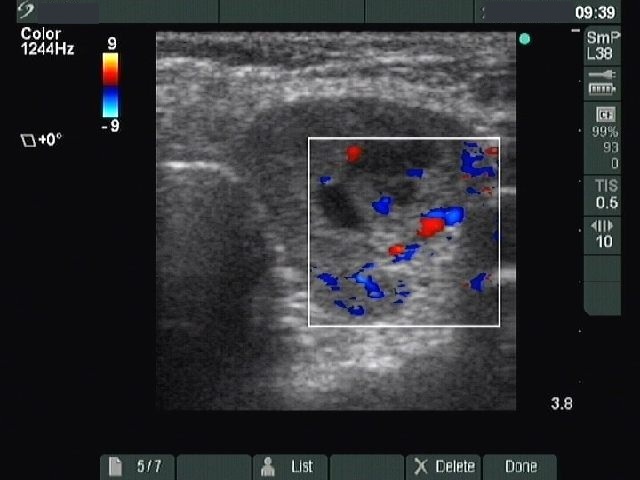

Benign nodular hyperplasia - Case 41. (ultrasonographic picture 5)

Left lobe, horizontal scan, color Doppler mode. The vascularization is increased.